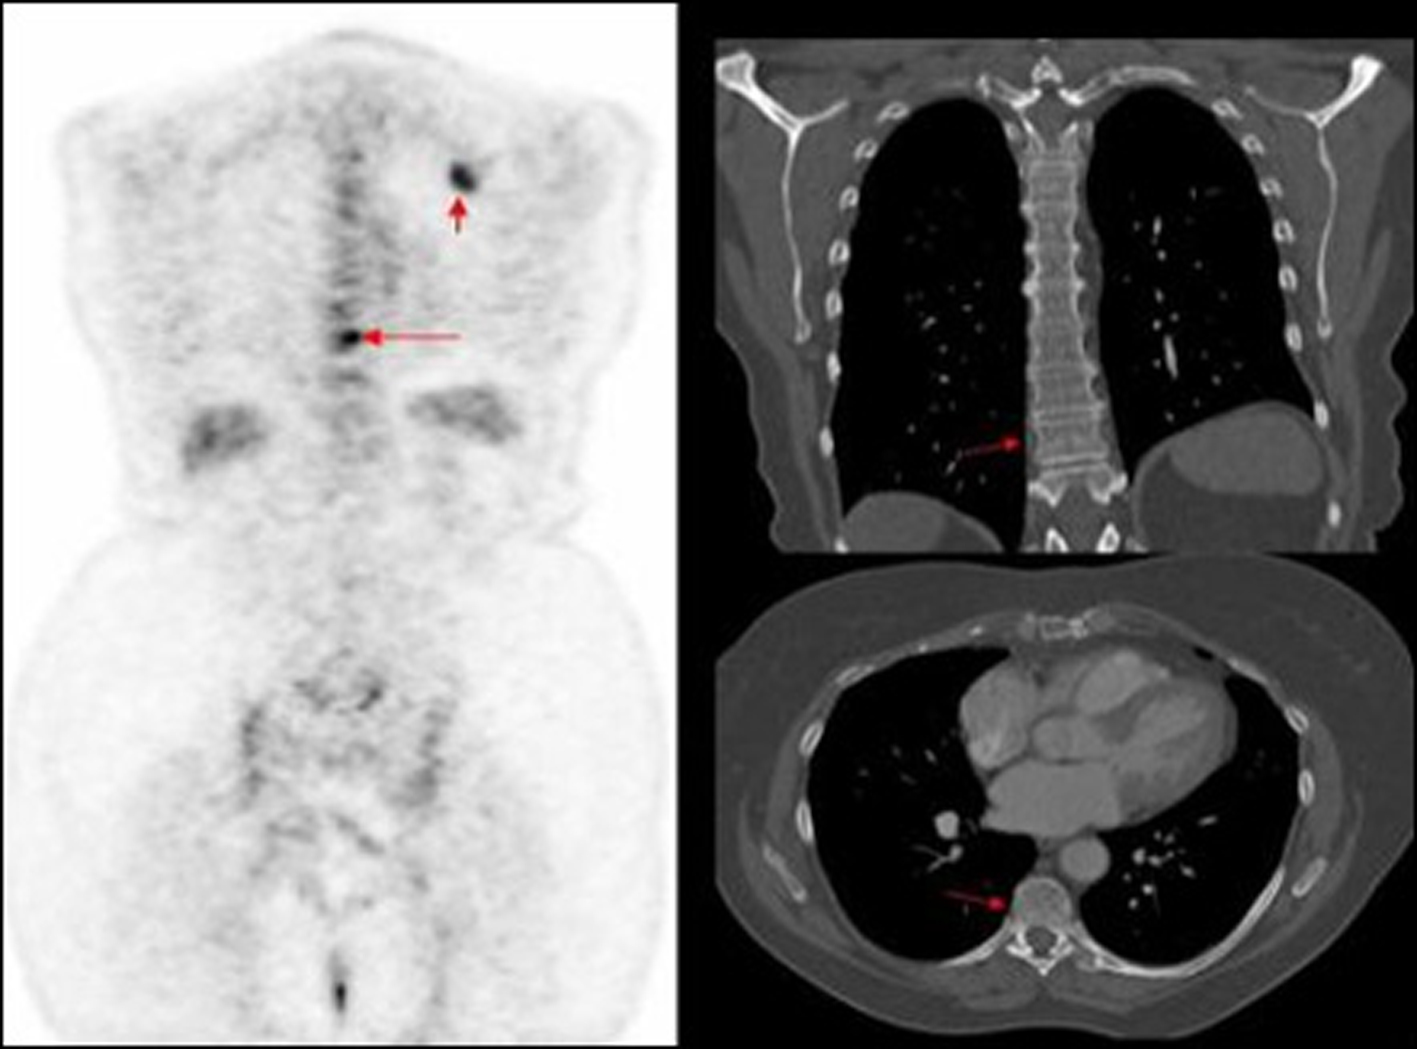

In our study nearly half of the in field metastasis were identified by two observers (Fig. 1). Most of the missed in field metastasis were bony involving the ribs, acromion and spine (Fig. 2, 3, 4). This could be explained by a number of reasons. Firstly it is easier to overlook a small bony metastasis especially in the ribs. Secondly, MIP (maximum intensity projection) reconstructions helps to depict the metastatic deposits better. If one does not routinely perform these, it might account for the missed deposits.

![]() Click for large image | Figure 3. PET image of thoracic vertebrae and left scapula metastatic deposits, not identified on corresponding CT. |